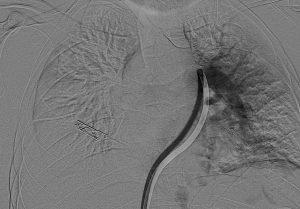

سجل مجمع الدمام الطبي أحد مكونات تجمع الشرقية الصحي ، إنجازاً طبياً نوعياً بعد نجاح فريق الأشعة التداخلية في إنقاذ حياة مريض كان يعاني من جلطة رئوية حادة وكبيرة شكّلت خطراً مباشراً على حياته ، وذلك باستخدام تقنية طبية متقدمة دون الحاجة إلى جراحة قلب مفتوح .

وكان المريض قد نُقل بشكل إسعافي من أحد المستشفيات وهو في حالة حرجة ، نتيجة معاناته من ضيق شديد في التنفس وانخفاض حاد في مستوى الأكسجين ، إثر انسداد كامل في الشريان الرئوي الرئيسي بسبب خثرات وريدية عميقة ظهرت بعد خضوعه لعملية منظار لمفصل الركبة.

وبفضل سرعة الاستجابة وجاهزية فريق الأشعة التداخلية جرى التدخل العلاجي العاجل وفتح الشريان الرئوي وسحب الجلطة بالكامل بدقة عالية ، ما أدى إلى تحسّن فوري في العلامات الحيوية واستقرار الحالة دون تسجيل أي مضاعفات.